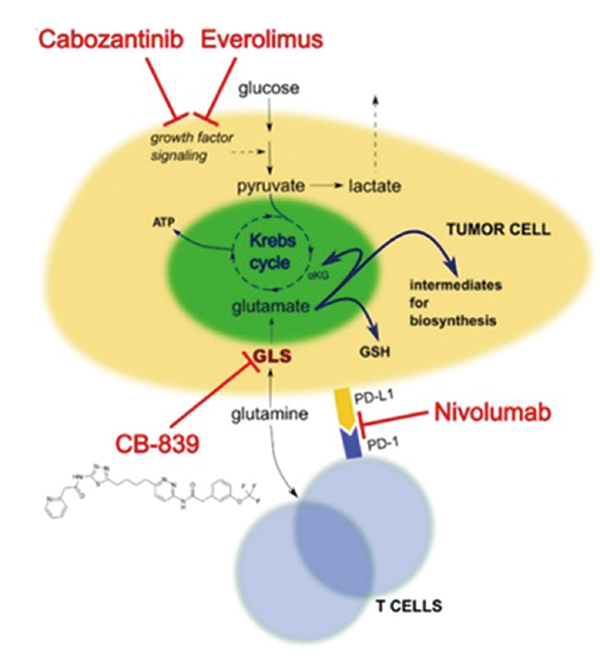

美国希望城综合癌症中心Pal等报告,治疗转移性乳头状肾细胞癌(RCC),多激酶抑制剂治疗卡博替尼对比舒尼替尼的中位无进展生存期(PFS)分别为9.0个月和5.6个月(HR=0.60,95%CI…

美国纪念斯隆·凯特琳癌症中心Motzer等报告,一线治疗晚期肾细胞癌(RCC)物,帕博利珠单抗-Lenvatinib改善了生存结局和缓解率,主要终点中位无进展生存期(PFS)达23.9个月,远…

美国纪念斯隆·凯特琳癌症中心Motzer等报告,与舒尼替尼一线治疗晚期肾细胞癌(RCC)相比,纳武利尤单抗联合卡博替尼有临床意义、疗效持久、生活质量改善。肉瘤样肾细胞癌患者…